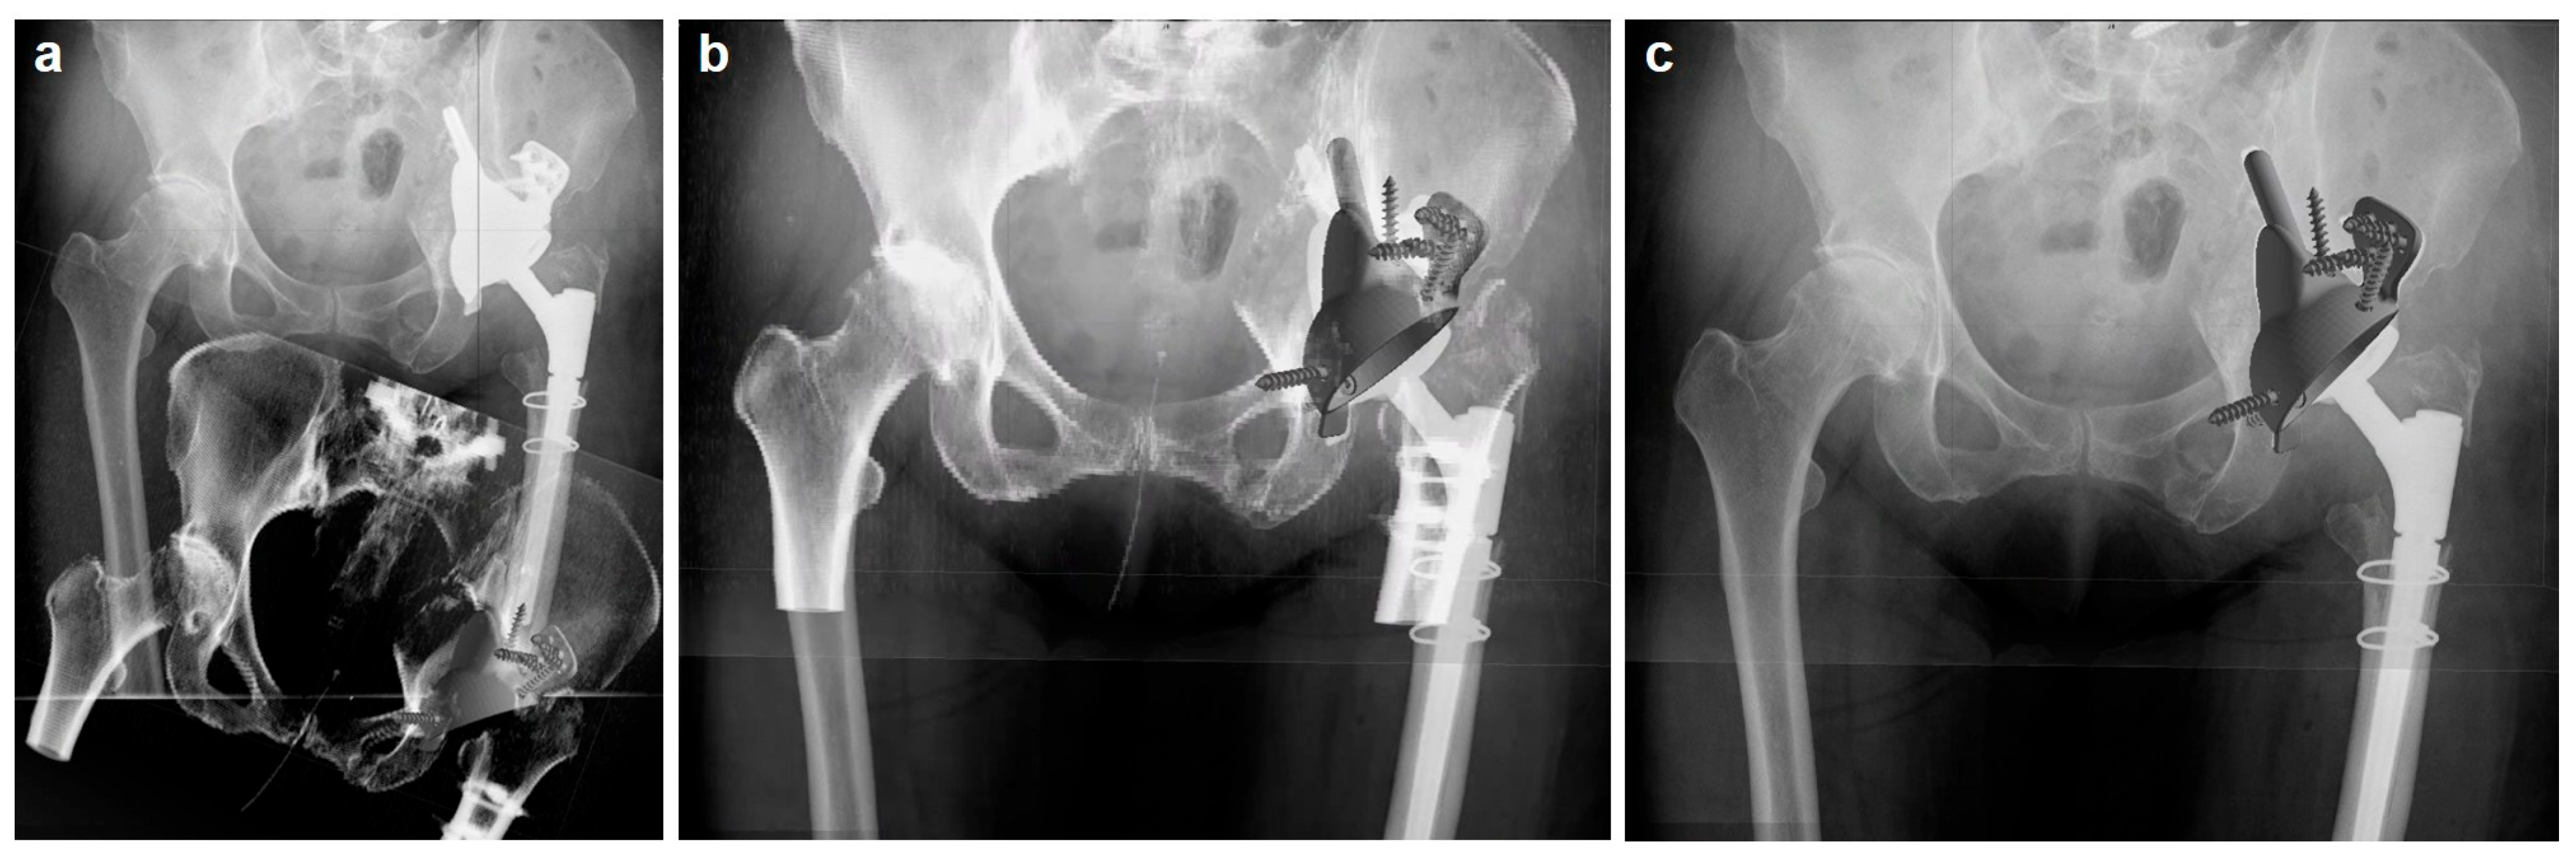

2.3. Custom-Made Acetabular Implants: Planning and Manufacturing

2.4. Surgical Procedure